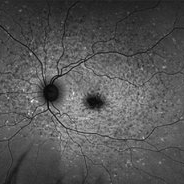

Late Stage Stargardt's Disease

Late Stage Stargardt's Disease

Mar 13 2013 by Hamid Ahmadieh, MD

Autofluorescence imaging of the left eye of a 46-year-old man with decreased VA due to advanced Stargardt's disease.

Photographer: Nayereh Hadipoor, Negah Eye Center, Tehran

Imaging device: Heidelberg Spectralis

Condition/keywords: autofluorescence imaging, Stargardt disease